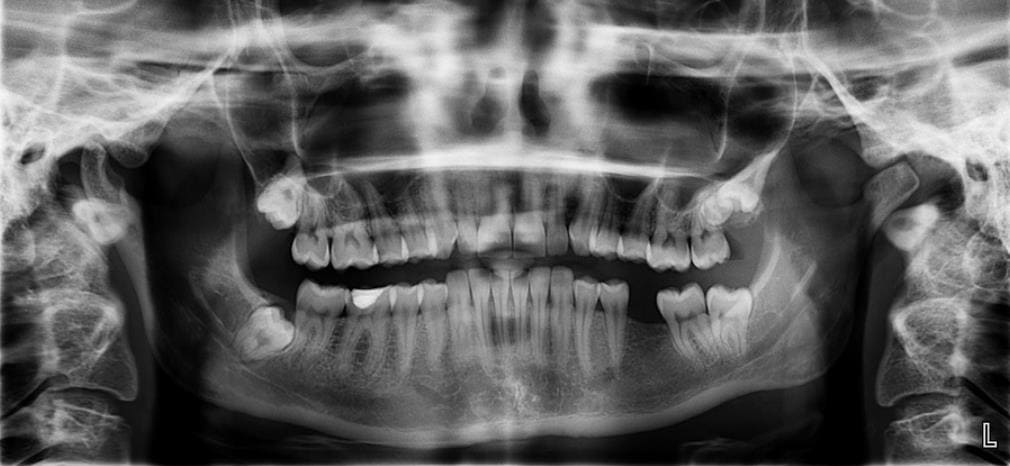

이번 포스팅은 사랑니와 어금니로 인한 잇몸이 부었을 때의 원인과 대처 방법 그리고 심할 경우에는 내려앉음 치료를 해야 하는지에 대해서 자세히 알아보도록 하겠습니다.

잇몸이 붓거나 염증이 생기는 이유는 평소 부실한 위생 습관과 충치에 의한 경우로 알려져 있으며 현대인의 대부분은 이와 같은 질환을 많이 겪습니다. 특히 관리를 제대로 해주지 못하였다면 잇몸에 통증이 나타난다거나 입에서 구취가 날 수 있고 평소 욱신거리거나 찌르는 듯한 통증이 반복적으로 지속되면서 잇몸에 부음 증상이 나타나 있다면 그것은 충치를 의심해 봐야 합니다.

충지가 생기고 나서 안쪽 깊숙이 퍼지게 되면 신경이 노출됨과 동시에 자연스레 잇몸에 통증을 주게 되고 더욱이 치아 뿌리에 고름을 만들어 악화시킨 다음 심각한 염증으로 발생할 수 있습니다. 따라서 상황에 따른 철저한 대처를 해주는 것이 좋습니다.

치주 질환은 잇몸 부음에 상당한 영향을 끼치는 2대 질환으로 알려져 있습니다. 치주 질환의 원인은 치구 내의 세균으로 인해서 감염이 되기도 하지만 30대 이상을 기준으로 흡연, 스트레스, 운동 부족, 당뇨병 등에 의한 면역력 저하 문제도 크게 관여하고 있습니다.

초기에는 치주 질환으로 인한 염증이 발생하여도 잇몸이 부었다고 하나 통증이 없어 인지하지 못하는 경우가 대개 있으며 이를 닦을 때 잇몸에서 피가 나는 경우도 종종 볼 수 있습니다.

특히 잇몸병으로 불리는 치주 질환은 치아 뿌리와 잇몸뼈 등에 염증이 생기는 병으로써 이는 치은염과 치주염 질환을 포함합니다. 대표적으로 사랑니가 있습니다. 치주 질환과 같은 염증 질환이 매우 심할 경우 치아를 전부 발치해야 될 수도 있는 상황이 올 수도 있기 때문에 평소 엄격한 관리를 통해 예방을 해주는 것은 필수적입니다.